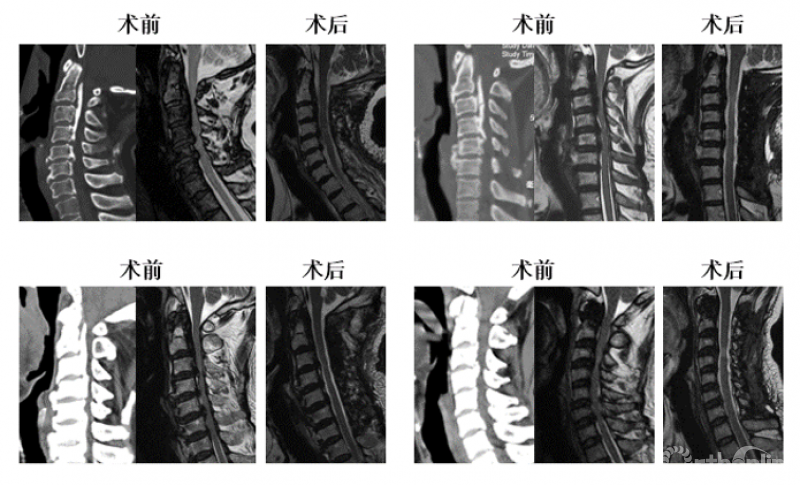

对于该例患者,C2/3间隙水平有轻度脊髓压迫,脊髓受压最重的节段仍然在C3/4水平。我们进行了再次手术,并向头侧扩大减压范围至C2,术后不仅C2/3水平的轻微压迫得到解除,C3/4水平脊髓压迫也明显去除了(图3),神经功能改善。

这个病例给我们的启示是:扩大减压范围至C2,有助于提高C3/4水平脊髓减压的效果。然而,显然并不是所有患者都需要扩大减压,那么需要回答的问题是:C3/4水平的脊髓前方致压物多大,需要扩大减压范围至C2?

图3 术后核磁显示脊髓减压充分

我们对57例患者的资料进行回顾,按减压节段分为C3-7组(n=32)和C2-7组(n=25)。测量并比较两组患者术后核磁上C2/3至C7/T1各节段脊髓前方至椎体后缘的距离(图4,在本研究中命名为脊髓前间隙,Anterior cord space, ACS),以了解不同的减压范围下减压效果的差异,以及将减压范围扩大至C2能带来的脊髓减压效果的获益究竟有多大。从而回答上述临床问题。

最后,我们回到病例一,利用上述研究结果指导临床决策:C3/4水平致压物中矢径8.71mm>7.1mm,所以C3-7减压势必残留压迫,应选择C2-7减压,术后获得了9.34mm的ACS,充分解除了脊髓压迫(图7)。

图7